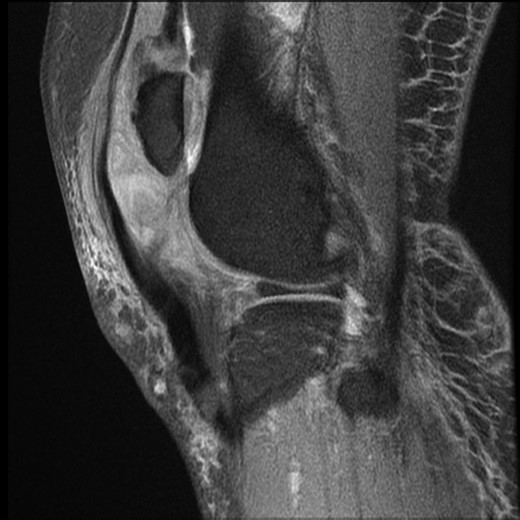

Physical examination showed knee swelling, a high riding patella with a palpable gap below the patella. The patient was unable to weight bear and could not perform active knee extension on his right knee. There was no obvious laceration or injury to the knee. Neurovascular examination was normal. Apart from ectopic ossification of the patellar tendon, plain radiograph showed no evidence of acute fracture or joint effusion (Fig. 1). Because of the unusual mechanism of injury and the initial ultrasound performed in A&E which suggested a rupture of the quadriceps and patella tendon, magnetic resonance imaging (MRI) was performed and demonstrated complete rupture of the patellar tendon from the inferior pole of patella, an almost complete shearing of quadriceps tendon off the patella and chronic tendinosis in the mid-portion of patellar tendon (Fig. 2).

MRI right knee. Sagittal T1 image. Demonstrating rupture patellar tendon attachment from inferior pole of patella, high riding patella, chronic tendinosis of patellar tendon and clustering of sheared quadriceps tendon.